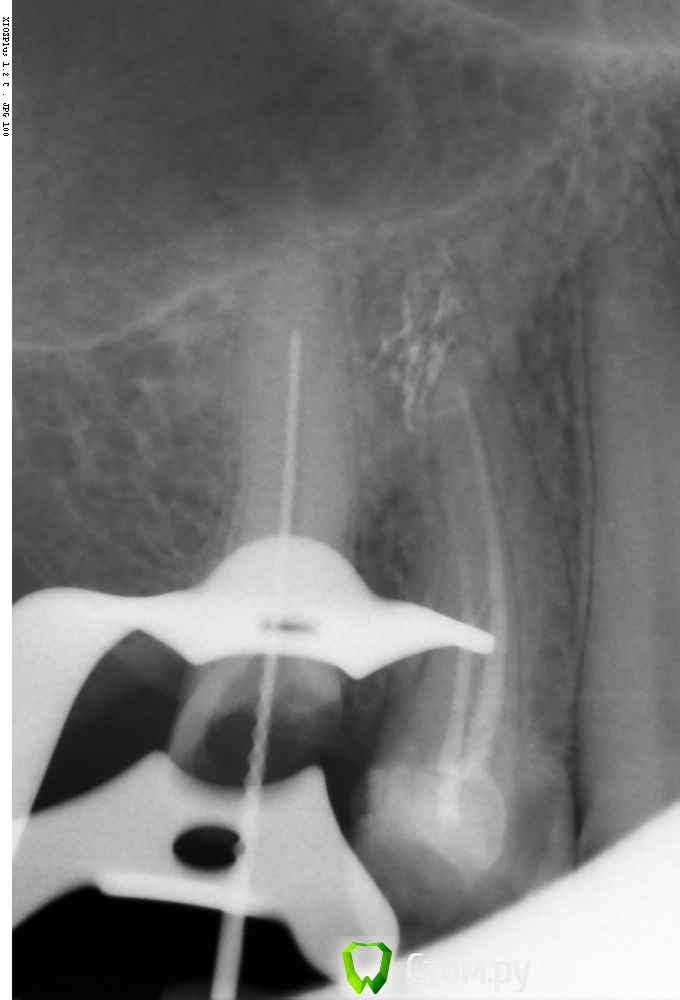

Shaid Опубликовано 18 мая, 2014 Поделиться Опубликовано 18 мая, 2014 (изменено) Вот какой тут будет прогноз?Долбил канал в два посещения. Петенси нет Изменено 18 мая, 2014 пользователем Shaid Ссылка на комментарий

Rash163 Опубликовано 18 мая, 2014 Поделиться Опубликовано 18 мая, 2014 Вот какой тут будет прогноз?Долбил канал в два посещения. Петенси нет Бессимтомник?Если да, то все будет хорошо) Ссылка на комментарий

Shaid Опубликовано 20 мая, 2014 Поделиться Опубликовано 20 мая, 2014 (изменено) Да. Ортопед направил перелечить. Пац ходит с кальцием сейчас, перкуссия слабоболезненна(до лечения безболезненно) Изменено 20 мая, 2014 пользователем Shaid Ссылка на комментарий